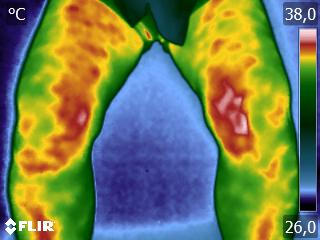

Como no caso da sequência de termogramas abaixo de uma paciente do sexo feminino, 42 anos, sem comorbidade e que apresentou dor em joelhos após treino de musculação. Foi realizado uma Análise Termofuncional e detectado alterações térmicas condizentes com o relato de dor.

Estas informações foram a oportunidade para convencer a paciente a realizar uma ressonância magnética para determinar o grau de comprometimento tecidual. Pois sem isso, após a melhora da dor, a liberação de carga e até a carga terapêutica ficariam limitadas.

Já com este conhecimento foi possível determinar um tratamento que abarcasse as áreas de dor e as áreas de comprometimento tecidual que apresentam inflamação, até a paciente retornar com o resultado da ressonância.

Isso adianta e muito a reabilitação, pois oferece informação que a olho nu não seria possível.